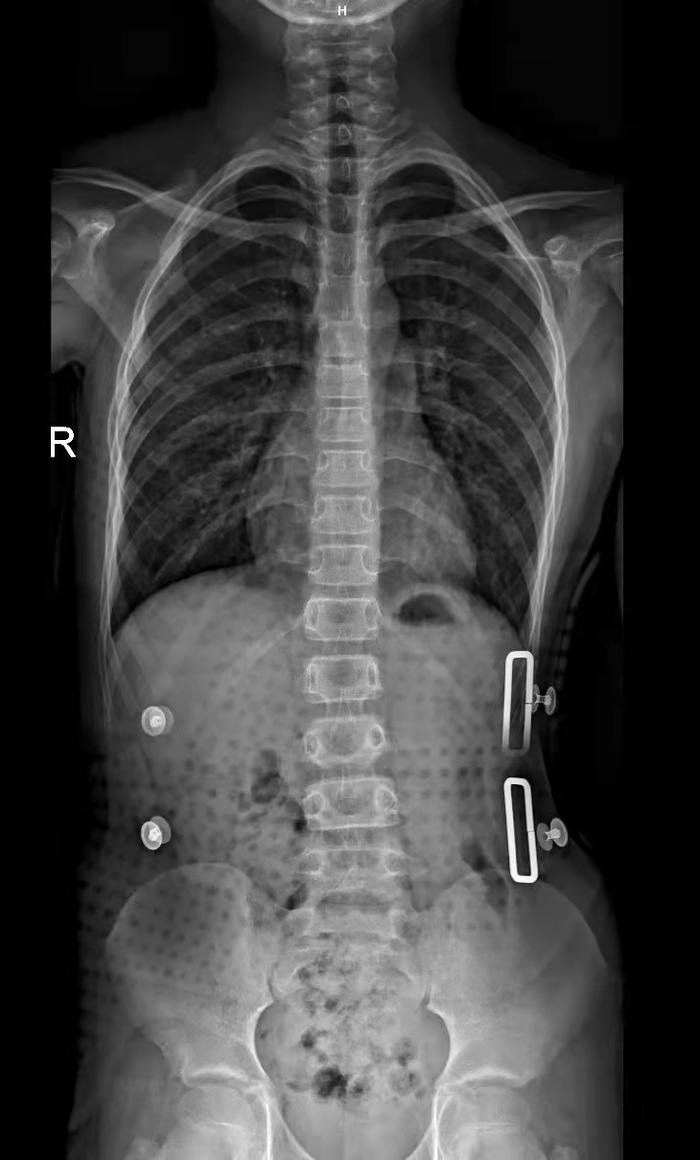

3D打印脊柱侧弯矫形器

传统脊柱矫形器的设计制作存在取型复杂、加工周期长等缺点;采用计算机辅助设计及3D打印脊柱支具具有个性化、矫正位置准确、设计制作时间短等优势,并且打印的支具具有质量轻、透气性好、舒适性佳等特点。

脊柱侧弯患者的侧凸类型、侧弯椎体、身材等结构均不同,个体差异大、矫形要求高,穿戴不合体的支具,易压迫患者侧弯部位,引起疼痛、压疮等问题,同时影响矫正效果。通过个性化设计及快速制造支具方案,获得满足患者个性化需求的支具,通过拓扑优化增加支具的透气性,降低患者皮肤由于封闭引起的压疮等风险。随着技术的推广和应用,利用计算机辅助设计,3D打印个性化医疗器械的前景十分广阔。